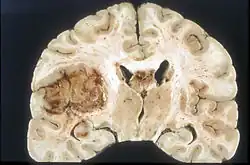

Das Glioblastom ist durch seine inhomogene und vielfältige (daher: multiforme) Erscheinung gekennzeichnet: die Tumorschnittfläche weist häufig rötliche Einblutungen und gelbliche Gewebsuntergänge (Nekrosen) auf.